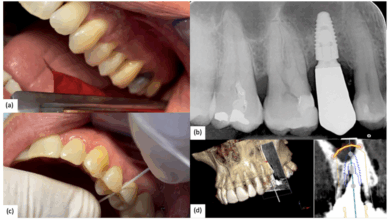

ایمپلنت لیزری دندان چیست؟ مراحل، مزایا، معایب و مراقبت های بعد از آن

ایمپلنت لیزری دندان یکی از جدیدترین روش های کاشت دندان است که با استفاده از تکنولوژی لیزر امکان قرار دادن…